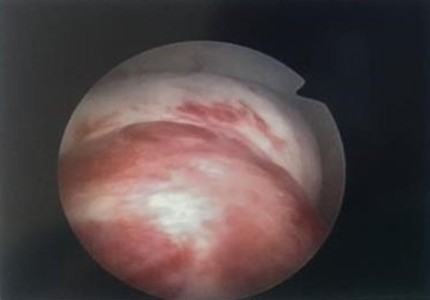

36歲的高小姐因為月經血量異常,輾轉來到花蓮慈院求診,經過門診子宮腔鏡檢查,才發現長了一顆約三公分的肌瘤,由於生長部位較為深層,所以,在其他醫療院所透過超音波並沒有明確發現肌瘤的存在,後續也藉由子宮腔鏡內視鏡手術,無傷口刮除肌瘤,陳萱醫師表示,經過切片檢查,證實為良性肌瘤。

陳萱醫師表示,子宮肌瘤是婦女常見的疾病之一,最常見的症狀就是月經大量出血或者點點滴滴來個不停等經血異常。而超音波檢查其實就有機會可以檢查出子宮肌瘤,只是有些肌瘤就像是高小姐一樣,生長在較深的肌肉層或漿膜層,不容易被發現,但是透過子宮腔鏡檢查就可以發現,進而早期治療。

圖:經過包含子宮腔鏡在內的檢查,陳萱醫師發現造成高小姐困擾的就是子宮內的肌瘤。